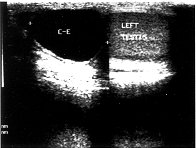

高频声像图:正常附睾表现为均匀细小回声,回声强度等于或略低于睾丸,头部呈新月形或钝圆的三角形。急性附睾炎,附睾体积增大,内回声不均匀或欠均匀,边缘清晰整齐,常合并睾丸鞘膜积液(本组发生率为50%),轻微加压探头,患者有明显压痛。而附睾慢性炎症内回声略高,不均匀,边缘呈现特征性“毛刺状”回声,无一例合并睾丸鞘膜积液。附睾结核由于其多样的病理基础,表现为高-低-无不均匀的混合性回声,有特征性强回声斑点后方伴声影(图1),而且与睾丸的界限不清,18例中仅2例合并睾丸鞘膜积液。精液囊肿声像图具有囊肿的共同特征,呈类圆形无回声区,后方回声增强,本组6例,最大3.6cm×2.6cm×1.7cm,最小直径0.5cm(图2)。精子肉芽肿2例,表现为比较均匀的低回声,边缘光滑整齐,与睾丸分界清晰(图3),较大的3.9cm×1.2cm。

图1 附睾结核 图2 附睾精液囊肿

彩色多普勒血流显像(CDFI):正常附睾可见少量点状血流分布。8例急性炎症均表现为增大的附睾内血流丰富,血管增粗,内径宽达2.7mm,血流速度加快Vmax 22cm/s(图4)。而慢性炎症、结核、精子肉芽肿等表现为少或无血流。

图4 急性附睾炎